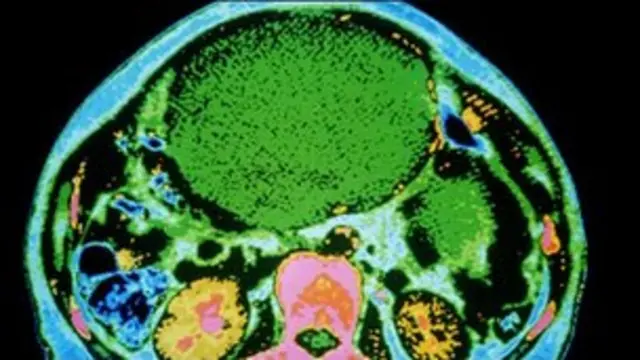

پیٹ میں چربی کینسر کے پھیلاؤ کا سبب

ایک نئی تحقیق کے مطابق پیٹ کے اوپر چربی کی تہہ رحم کے کینسر کو پھیلانے میں مدد فراہم کرتی ہے۔

رحم یا بیضہ دانی کے کینسر کے اسّی فیصد کیسز میں بیماری کی تشخیص سے پہلے ہی کینسر پیٹ پر موجود چربی کی اس تہہ تک پہنچ جاتا ہے جسے اومینٹم کہا جاتا ہے۔

دی نیچر میڈیسن ریسرچ نامی رسالے کا کہنا ہے کہ اگر رحم کا کینسر جسم میں اومینٹم تک پہنچ جائے تو یہ بیماریچربی کی اس پُوری تہہ کو اپنی لپیٹ میں لے لیتی ہے۔

اومینٹم پیٹ کے اُوپری حصے میں پایا جاتا ہے اور اگرچہ یہ اپنے ارد گرد موجود اعضاء کو سہارا دیتا ہے لیکن جسم میں اس کا ہونا کوئی ضروری نہیں ہے۔

اکثر ایسا ہوتا ہے کہ اومینٹم میں اس کینسر کا پھیلاؤ ابتدائی پھیلاؤ سے زیادہ بڑھ جاتا ہے تاہم یہ معلوم کرنے کے لیے امریکہ میں یونیورسٹی آف شکاگو کی ایک ٹیم نے چوہوں پر تجربہ کیا جس سے واضح ہوا کہ یہ کیسنر اومینٹم تک بیس منٹ کے اندر داخل ہو جاتا ہے جس کے بعد یہ اومینٹم میں موجود چربی کو استعمال میں لا کر مزید بڑھتا رہتا ہے۔